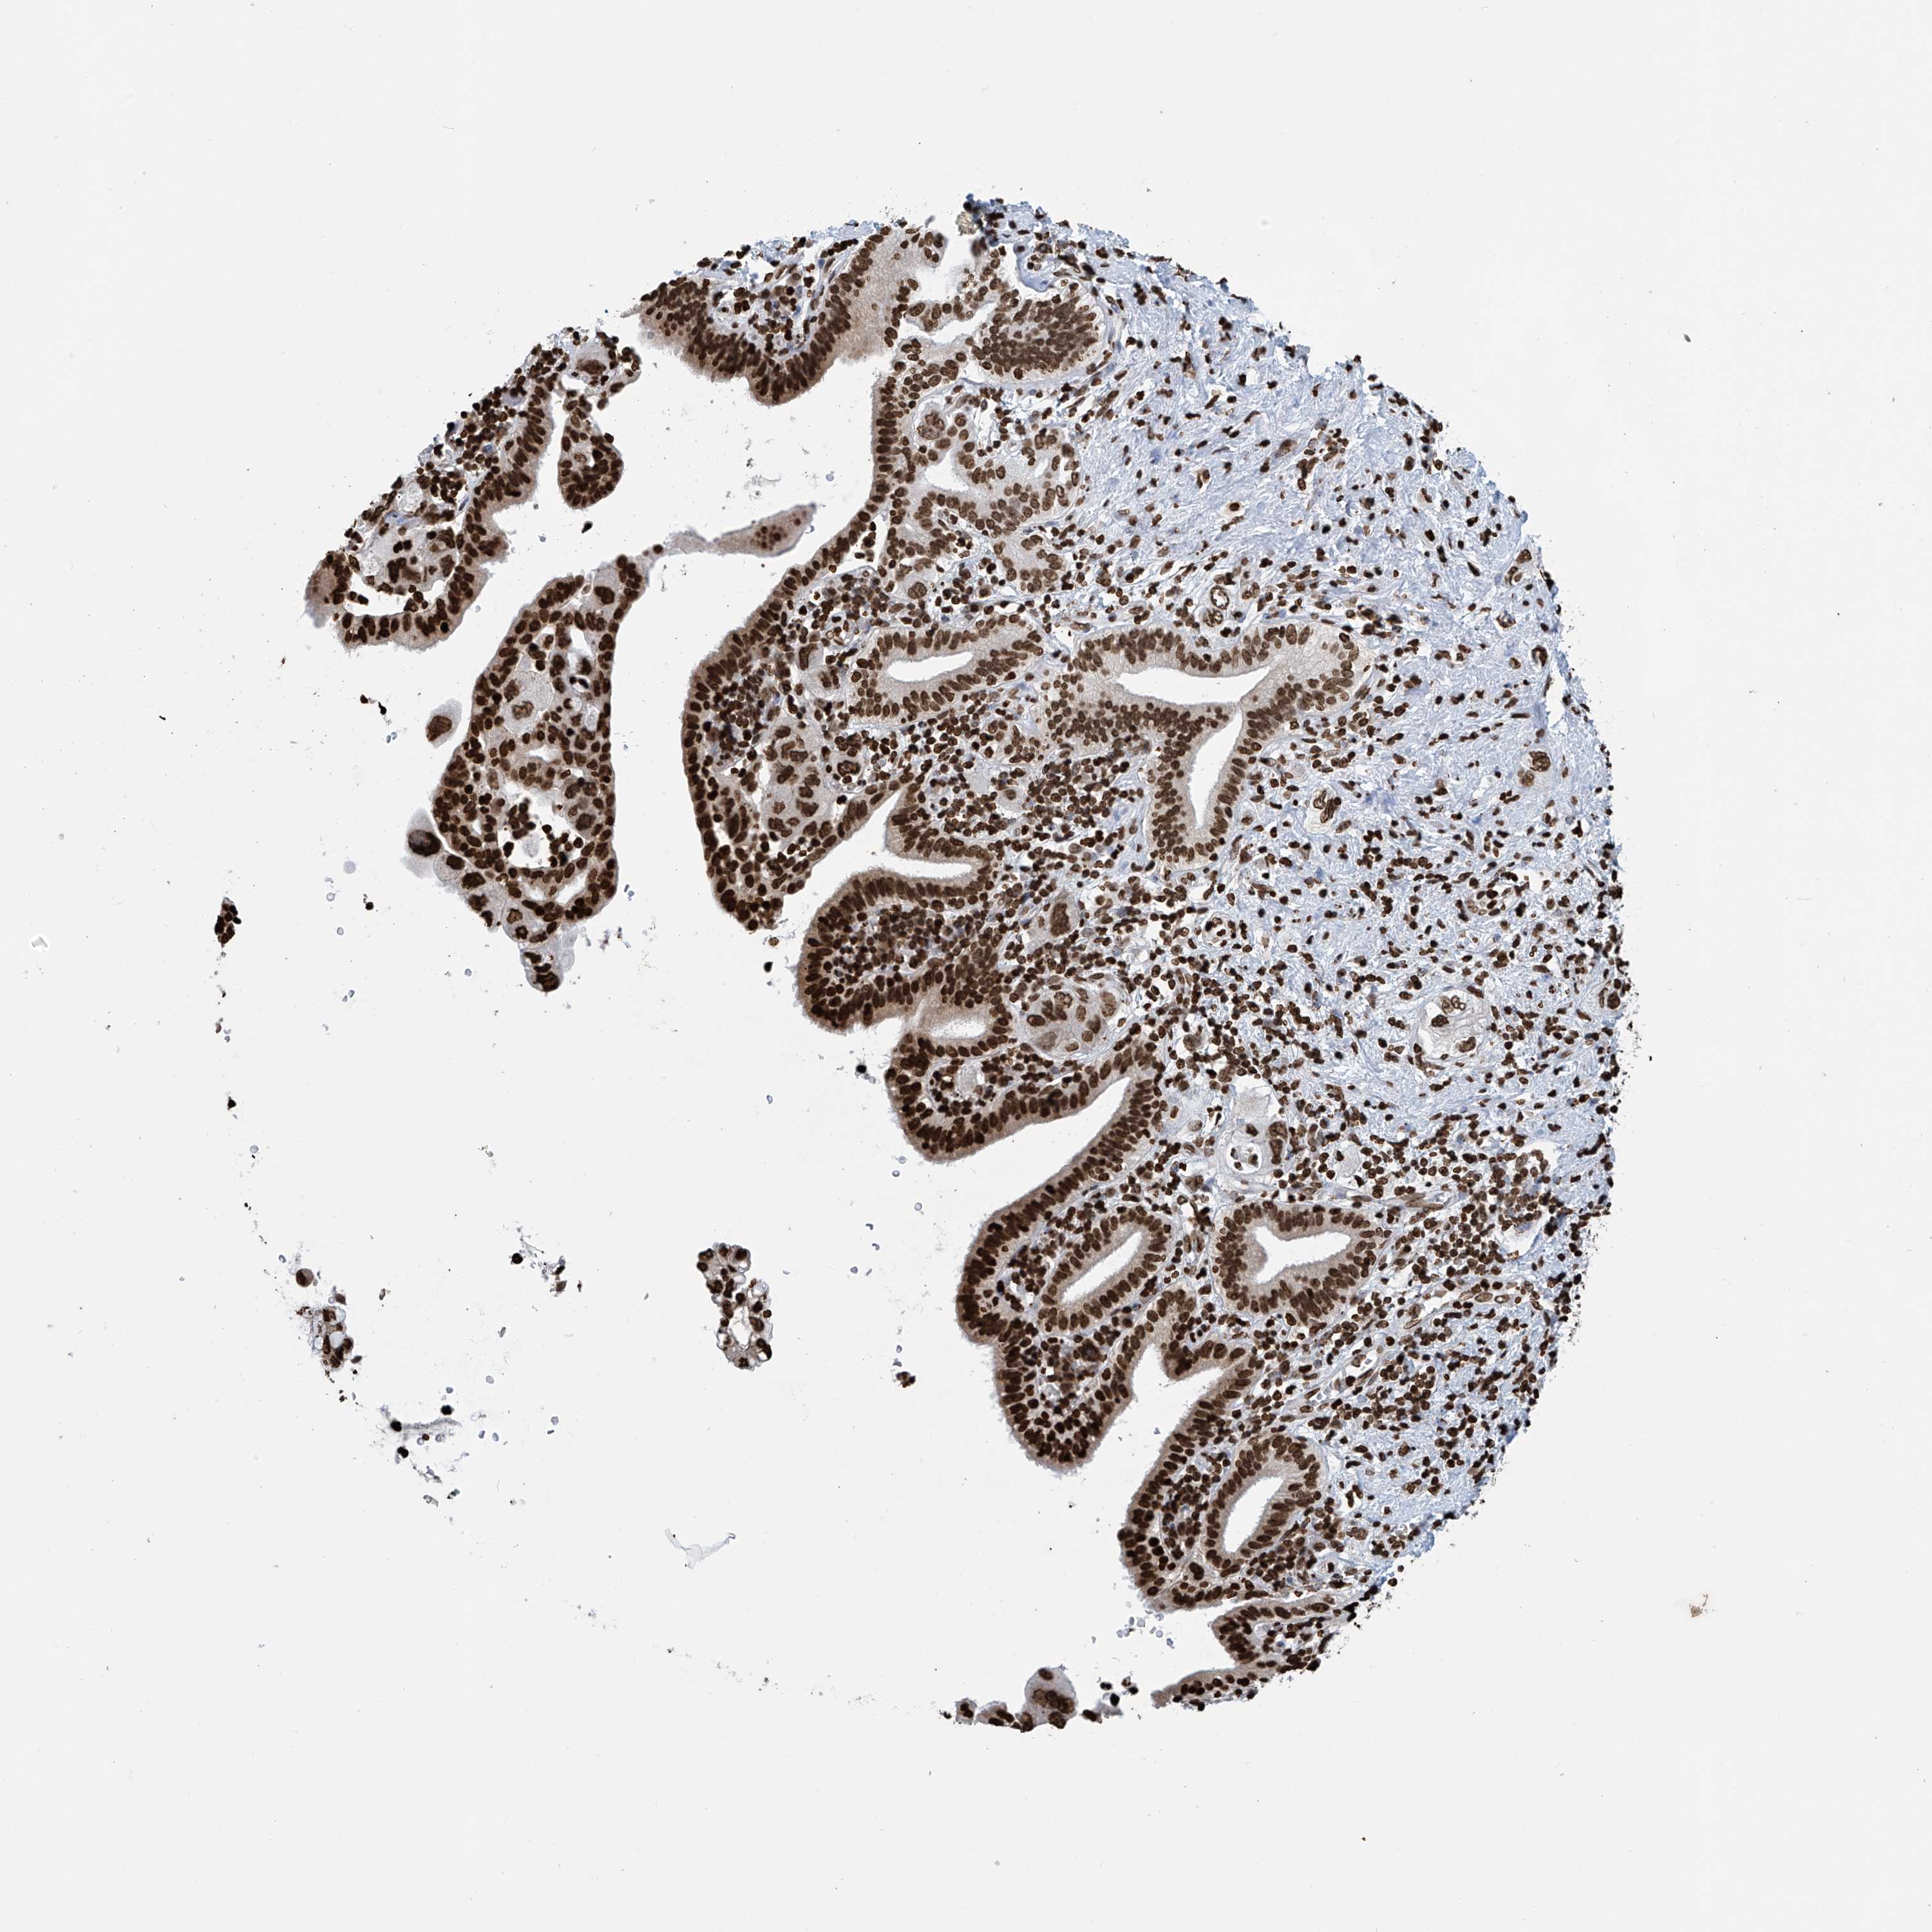

PANCREATIC CANCER - Protein expressioni

A mouse-over function shows sample information and annotation data. Click on an image to view it in a full screen mode. Samples can be filtered based on level of antibody staining by selecting one or several of the following categories: high, medium, low and not detected. The assay and annotation is described here.

Note that samples used for immunohistochemistry by the Human Protein Atlas do not correspond to samples in the TCGA dataset.

Antibody stainingi

Antibody staining in the annotated cell types in the current human tissue is reported as not detected, low, medium, or high, based on conventional immunohistochemistry profiling in selected tissues. This score is based on the combination of the staining intensity and fraction of stained cells.

Each image is clickable and will lead to virtual microscopy that enables deeper exploration of all samples and also displays staining intensity scores, fraction scores and subcellular localization as well as patient and tissue information for each sample.

Antibody HPA036134

Staining

High

Medium

Low

Not detected

Intensity

Strong

Moderate

Weak

Negative

Quantity

>75%

75%-25%

<25%

None

Location

Nuclear

Cytoplasmic/membranous

Cytoplasmic/membranous,nuclear

Adenocarcinoma, NOS